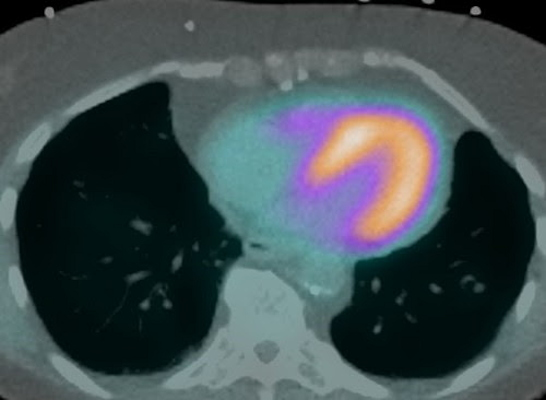

新指南中的一張圖顯示了PET圖像在CT衰減校正掃描中的正確配準。圖片由ASNC提供。